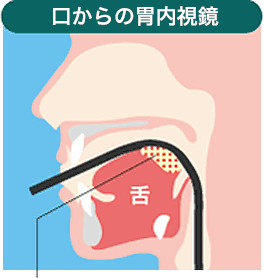

鼻から胃カメラの特長

- 話せる

- 医師と同じ画像を見ながらリアルタイムで話せる。

- 嘔吐感が起きにくい

- スコープが舌の付け根に触れない。

- 苦痛が少ない

- 直径5.9mmの細くしなやかなスコープ。

- 麻酔事故のリスクが少ない

- 鼻腔への麻酔だから、身体への負担が軽い。

この部分にスコープが触れると、

吐き気を感じます。

この部分にスコープは

触れにくい。

また、 患者は医師と会話することができるため、モニターを見ながら医師に質問できるなど安心した診療を受けることができます。